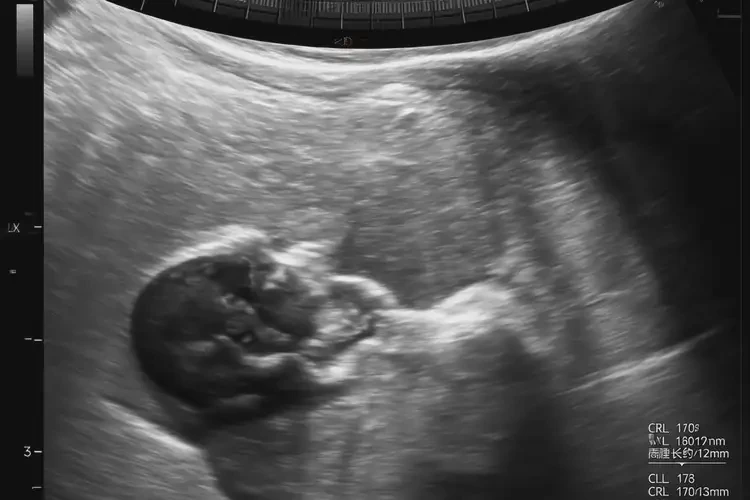

孕7周6天胎心110左右正常嗎(圖1)

胎心率在孕7周6天時(shí)約為110次/分鐘,屬于正常范圍。

在孕7周6天時(shí),胎兒的胎心率通常在100-170次/分鐘之間波動(dòng),因此110次/分鐘左右的胎心率是正常的。胎心率會(huì)受到多種因素的影響,包括胎兒的活動(dòng)水平、孕婦的情緒和身體狀況等。以下是關(guān)于孕7周6天胎心率的詳細(xì)信息: